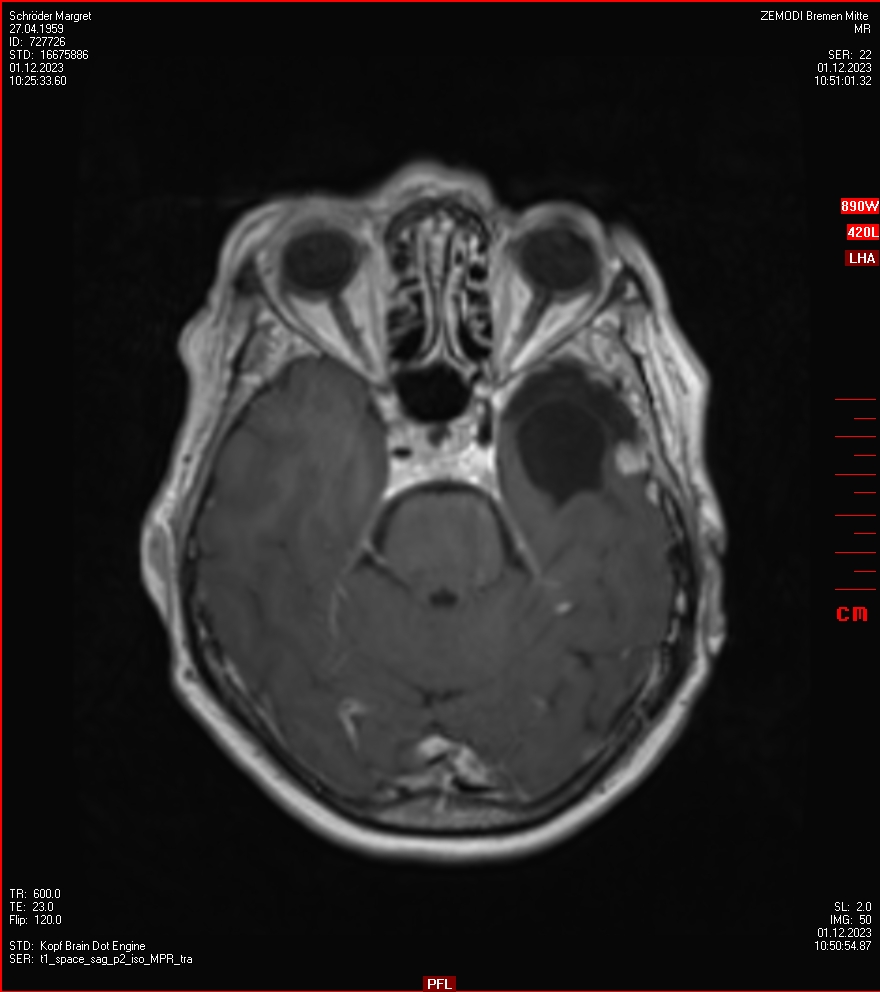

Zum Vergleich nun auch die Bilder vom 1.12.2023:

Ich denke, in den letzen 12 Monaten sind da ein paar Rezidive gewachsen,  vor 12 Monaten waren sie auch schon zu erkennen - vorher noch nicht. Nun hoffe ich auf den Rat des Spezialisten. Hoffendlich kann man etwas machen.